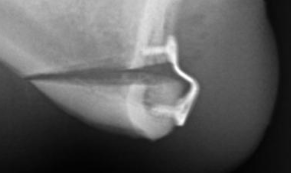

1770627749810

1770627816843

Bro you gotta be fucking kidding me @sayonara @Gargantuan nigga better sue his surgeon atp

You ascended judging from your X-rays. You just need to wait until your swelling fully goes away.